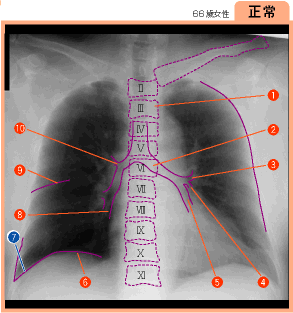

▲130ページ 正常画像内(2007/2/5)

※7の引き出し線の位置が誤っておりました(下は修正済みの画像です.青い線で示しています)

| ● |

|